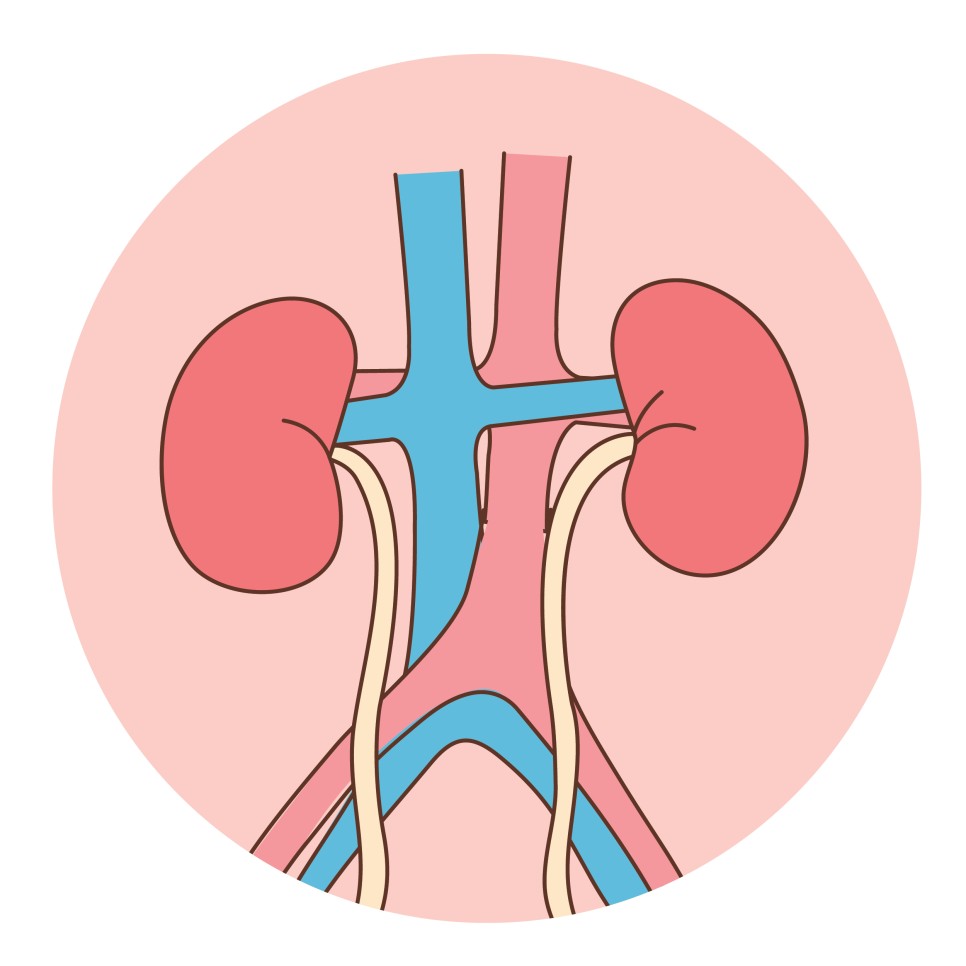

단백뇨, 만성콩팥병

고혈압의 영향으로 콩팥으로 가는 동맥이 경화되고 점차 콩팥 기능이 약해지면 신경화증, 신부전증, 단백뇨, 만성콩팥병 등을 유발할 수 있습니다.